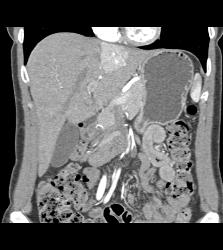

Focal Nodular Hyperplasia (FNH)